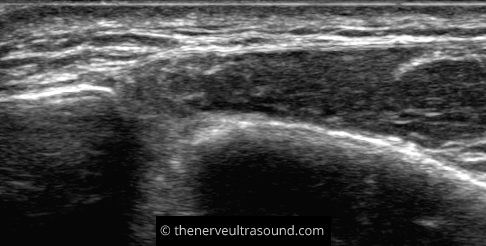

The superficial peroneal nerve finally pierces the fascia to run subcutaneously. It subsequently divides into the medial dorsal cutaneous nerve and the intermediate dorsal cutaneous nerve.